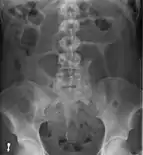

After taking a thorough history, the diagnosis of colonic volvulus is usually easily included in the differential diagnosis. Abdominal plain x-rays are commonly confirmatory for a volvulus, especially if a "bent inner tube" sign or a "coffee bean" sign are seen. These refer to the shape of the air-filled closed loop of colon which forms the volvulus. Should the diagnosis be in doubt, a barium enema may be used to demonstrate a "bird's beak" at the point where the segment of proximal bowel and distal bowel rotate to form the volvulus.